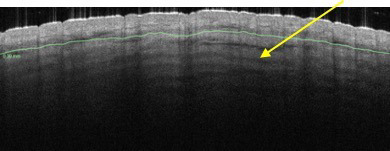

FIGURE 18.

Side-view optical coherence tomography image of striae distensae showing dark banding parallel to skin surface (arrow) attributed to birefringence of highly organized collagen to considerable depth.

Dermis. The most insightful part of our analysis of striae using OCT imaging was in observing the dermal collagen distribution in these scars. Striae had long been thought to be superficial but OCT revealed banding to a depth of at least 800µm (Figure 18). This banding may be attributed to optical birefringence due to highly organized collagen fiber bundles arranged in organized, unidirectional layers, rather than in the normal basket-weave pattern of collagen bundles in healthy skin. These observations suggest that striae are not superficial, but comprise deep layers of dense organized collagen.